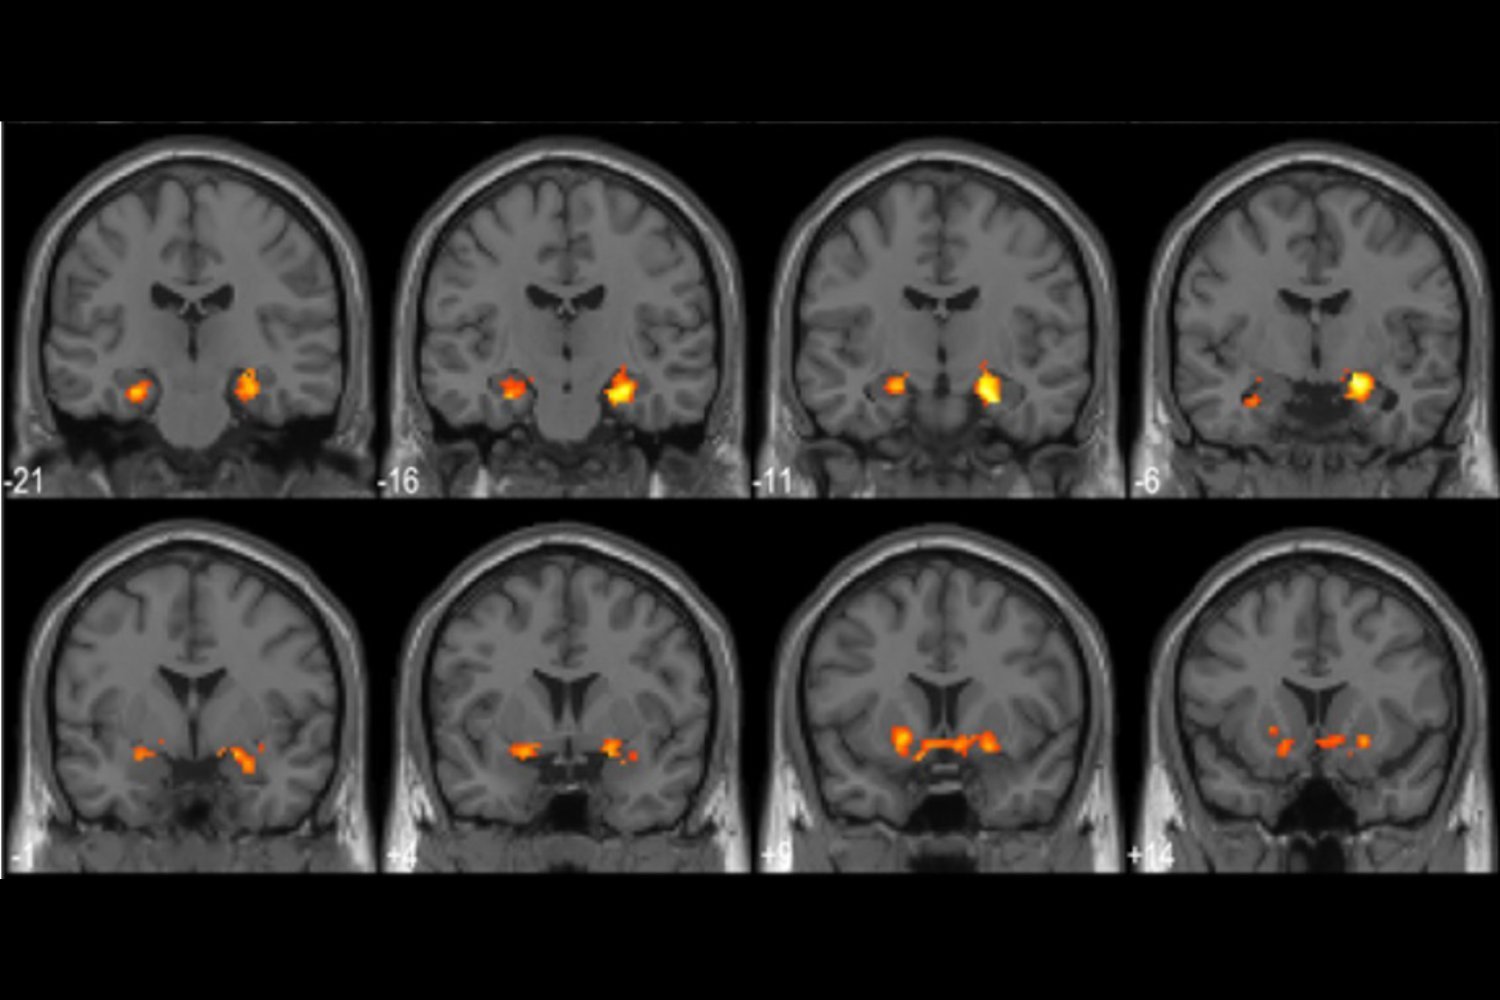

Effective magnetic resonance imagery shows that epiphanies explode in hippocampus, a part of the brain involved in learning and memory. The powerful moments of insights cause strong explosions of the activity. When the participants solve the puzzle and eventually recognize the secret object, the researchers also mentioned the change in the Neuron Firing Dynamics, especially in the Ventral OcePTo-Typoral Cortex region, which are involved in recognizing visual patterns. Similarly, the stronger the moment of insight, the more researchers have changed.

“During these moments of these insights, the brain re -organizes how it shows the image,” Maxi Baker, the first author of Humblet University study and a cognitive neurologist. Furthermore, researchers associated the more powerful epiphanic with more connections between those parts of the brain. “Different territories interact with each other more efficiently,” said the cabza.